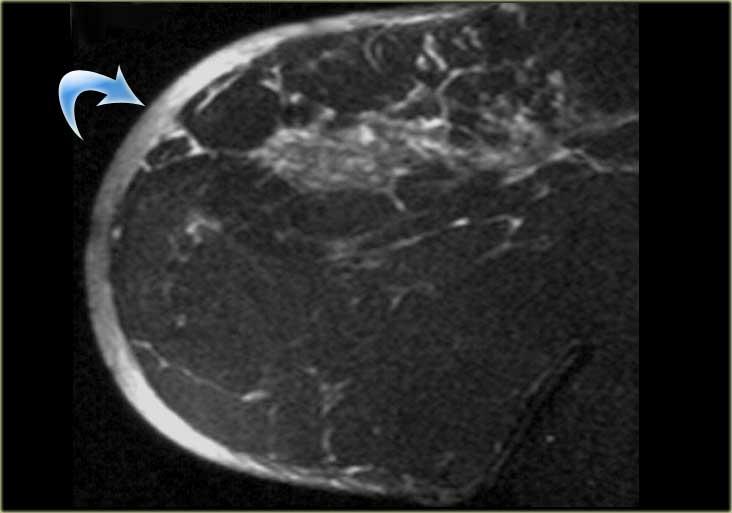

Bên trái là hình ảnh cho thấy một khối lớn, hình tròn với bờ nhẵn, được xác định là nang vùi biểu bì.

Hình ảnh ngoài cùng bên trái cho thấy một khối có bờ tua gai, tức là khả năng ác tính 80%.

Bên cạnh đó là mẫu bệnh phẩm đại thể tương ứng.

Có thể thấy các tua gai xâm lấn vào mô xung quanh trong cả hai hình.

Tương tự như trên nhũ ảnh, tổn thương này có khả năng ác tính cao và sẽ được phân loại BIRADS 5.